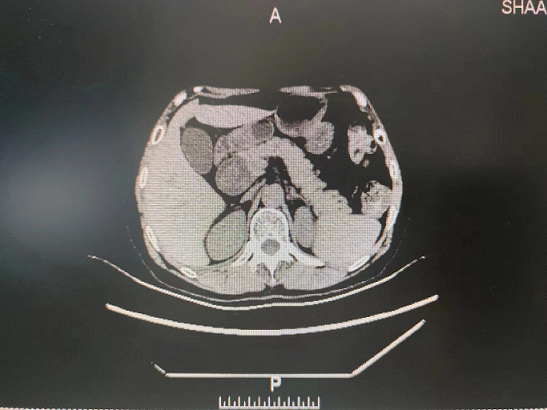

患者5月9日来六合彩生肖就诊,门诊以“胆总管囊肿”收住院。入院后予完善相关检查后诊断:1.胆总管囊肿(Ⅰ型)并胆总管结石2.胆管炎?。随后给予抗炎、补充电解质,营养风险评估,营养支持等治疗,组织专家进行围术期术前评估、讨论,制定手术计划方案并征得家属和本人同意后,5月15日在普外科田德福主任的带领下,在任斌副主任、杨洲明主治医师的配合下及麻醉科的协助下,对患者行胆总管囊肿切除+胆总管空肠ROU-en-Y吻合术,手术顺利,病理结果提示无癌变。术后在何慢护士长团队的精心护理下,患者第2天就下床活动,第4天进流食。术后没有发生腹腔感染、出血、吻合口漏等相关并发症,术后相关实验室检查结果无异常,5月29日患者痊愈出院。

外科第一党支部书记、普外科主任田德福主任医师表示,胆总管囊肿为先天性胆总管囊状扩张症,发病率低,可以并发结石、有癌变的可能,手术治疗是主要治疗手段。胆总管囊肿切除需要做到胆总管囊肿切除+胆总管空肠ROU-en-Y吻合术,在普外科手术中属难度较高的四级手术,开展这一高难度手术,对普外科医生来说具有很大的挑战性,不但要求具备精湛技术,更需要对患者高度负责的精神。此次手术的成功开展使得医院普通外科在高难度肝胆外科领域得以进一步拓展,同时也增加了科室进一步拓展此项技术的信心。